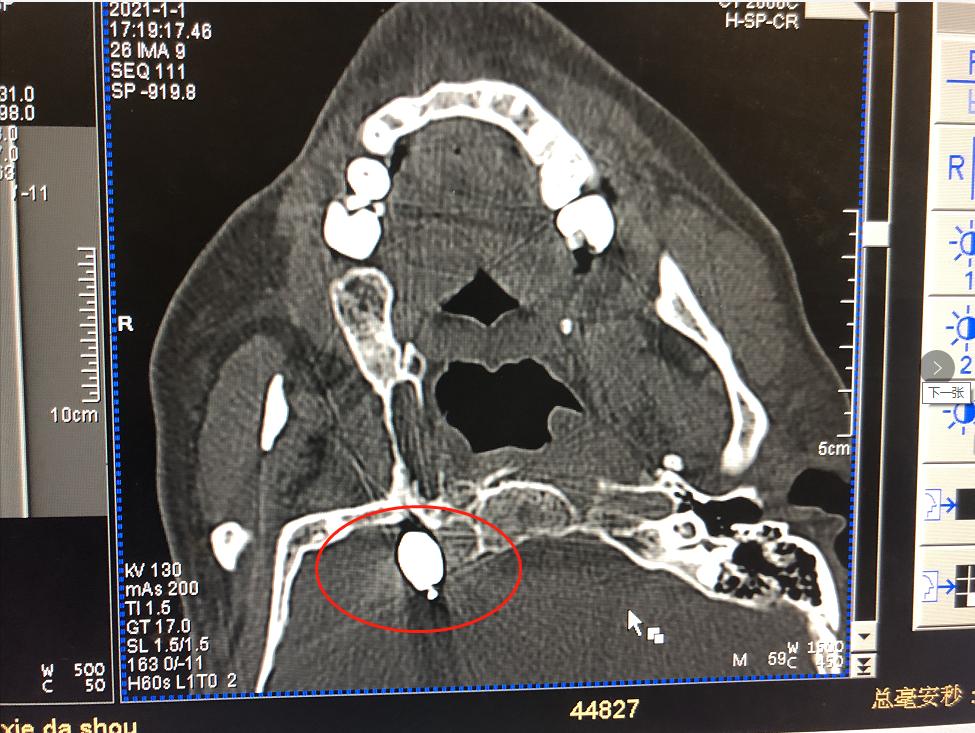

疼痛来得快,也去得快。缓过劲来的刘大伯到附近医院去看医生,被诊断为三叉神经痛,医生为他开了药。早期还有些效果,疼痛很快就能缓解,渐渐地,疼痛变得如影随形,不经意间便又冒出来,说话、吃饭、洗脸、刷牙等生活中常见的行为均可诱发疼痛。 无奈之下,饱受疼痛折磨的刘大伯去了芜湖的多家医院求治,疼痛科、神经内科就诊,基本上都是进行药物治疗,疼痛时好时坏。由于长期大剂量服药,药物治疗的副作用越发显现,这让他苦不堪言,严重影响了他的生活质量。 02不到20分钟的微创手术,彻底解除疼痛烦恼 最近,刘大伯的疼痛发作更频繁了,一吃东西就痛,痛起来更是痛不欲生,根本吃不了东西,被折磨得有气无力。 刘大伯慕名来到我院疼痛科就诊。疼痛科的秦学智主任了解了刘大伯的病情后,秦主任根据他的病史和身体情况,与团队进行了缜密分析和探讨,决定为其实施球囊压迫术解除三叉神经痛。 经秦主任详细解释后,刘大伯和家人欣然同意接受手术。 微球囊压迫术 微球囊压迫术被称为“针尖内的手术”,整个创口仅一个针眼大小,操作时间短,此次手术在局部麻醉下进行,患者全程为清醒态势,此手术具有创伤小、风险小、见效快、恢复快、复发率低的优点。 术中定位进针球囊进入

术中定位

进针

球囊进入